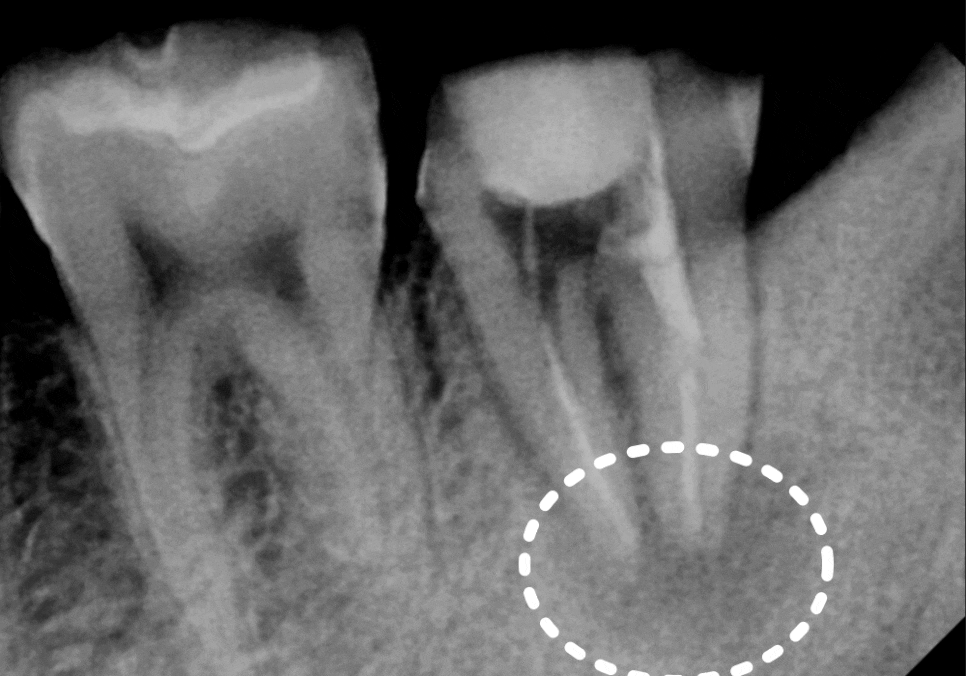

얼마 전 1년 전 신경치료를 받았던

오른쪽 아래 어금니(#37) 문제로

한 환자분이 내원하셨어요.

뿌리 염증 때문에 타병원에서

발치 후 임플란트 권유 받으셨다고 하는데,,

CT상에서도 뿌리 염증이 꽤 진행되어 있었지만,

260220

환자분의 살리고자 하는 의지가 강하셨기에

시간을 들여 재신경치료를 시작했습니다.

한 달 뒤,

시꺼멓게 보이던 뿌리 끝 염증이

눈에 띄게 사라진 모습!!

260219 / 260324